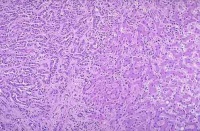

3.肝外胆管癌的组织学类型:根据癌细胞的类型分化程度及癌组织生长方式肝外胆管癌可分为以下6型:

①乳头状腺癌:除个别为管壁浸润型外几乎均为腔内乳头状型

②高分化腺癌:在胆管癌中最多可占2/3以上可见于任何部位癌组织均在管壁内浸润生长环绕整个管壁浸润的癌组织呈大小不等形状不规则的腺体结构有的可扩大呈囊腔

③低分化腺癌:即分化差的腺癌癌组织部分呈腺体结构部分为不规则的实性片块亦在管壁内弥漫浸润生长

④未分化癌:较少见有的小细胞未分化癌与胆囊的未分化癌相同癌细胞在胆管壁内弥漫浸润间质较少癌组织侵袭较大常可侵及胆管周围脂肪组织或邻近的器官

⑤印戒细胞癌:较少见它与胆囊或胃肠道的印戒细胞癌一样由分化程度不等的含有粘液的癌细胞构成癌细胞无一定结构弥漫浸润

⑥鳞状细胞癌:罕见其组织形态与其他器官所见者相同